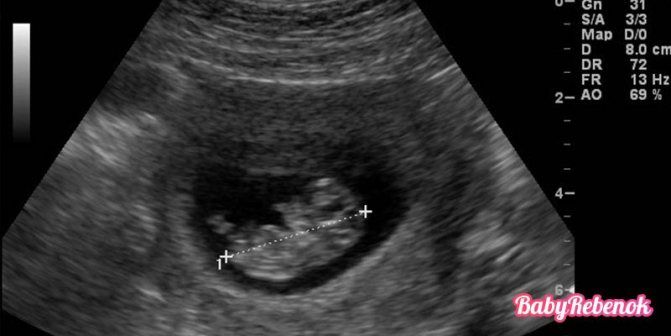

Что покажет УЗИ на 10 неделе беременности. Фото плода

На 10 неделе беременности обычно не проводят УЗИ без каких-то особенных показаний. Обычно контрольное исследование назначают на период между 10 и 14 неделями. Но если сделать УЗИ на 10 неделе, можно увидеть, что плод уже похож на человека. Если он не спит, то активно шевелится, двигает ручками и ножками, может брать пальчик в рот. Плод находится в пузыре, наполненном амниотической жидкостью.

Фото УЗИ на 10 неделе беременности